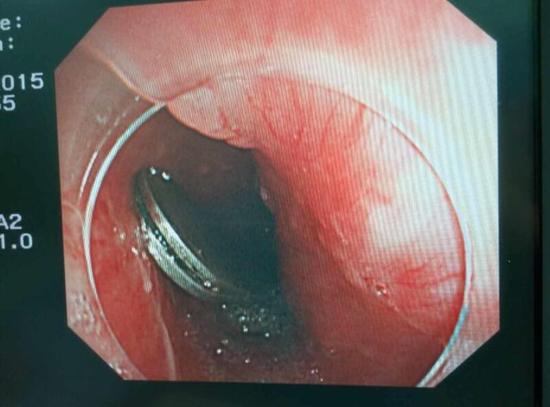

手術(shù)中,范醫(yī)生通過胃鏡準確發(fā)現(xiàn)了胃里的鑷子。但讓他驚訝的是,在華先生胃底竟然還躺著三個被腐蝕了的打火機,打火機的金屬部件都已經(jīng)不見了。

隨后,范醫(yī)生先用圈套器套取出了長10厘米的鑷子,再一個一個地取出了打火機。整個取出過程小心謹慎而又一氣呵成,只用了不到10分鐘。